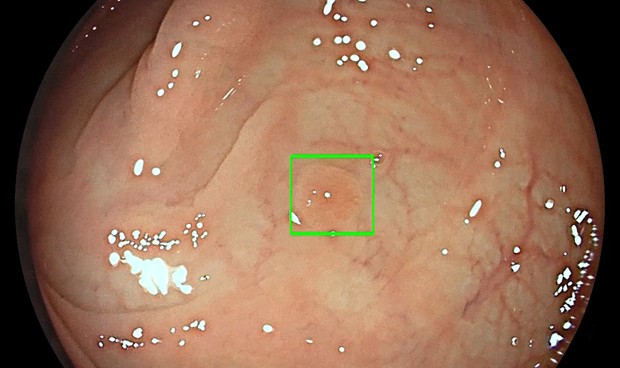

Detección de pólipo mediante inteligencia artificial.

Medtronic, líder mundial en tecnología médica, ha desarrollado esta tecnología que detecta lesiones precancerosas con un marcador visual en tiempo real que funciona como un segundo observador.

“Medtronic dedica especial atención a la prevención del cáncer colorrectal mediante la detección precoz de pólipos precancerosos con tecnologías asistidas por IA", señala Giovanni Di Napoli, vicepresidente y director general de la unidad de Gastrointestinal y Hepatología de Medtronic. "Nuestro sistema detecta los pólipos automáticamente, incluso pequeños pólipos planos que pueden pasar desapercibidos, aumentando así la precisión y reduciendo el riesgo de cánceres de intervalo, que se pueden producir entre colonoscopias", declara Di Napoli.